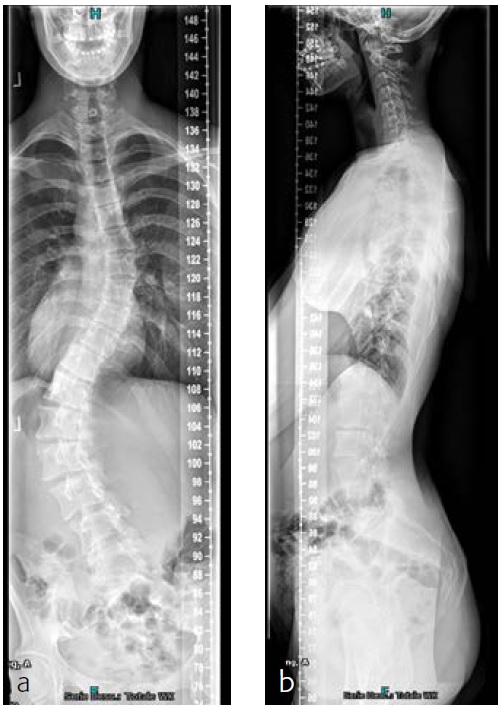

The patient was known and under orthopedic control for a Lenke 5C-type AIS since 2009. Initial treatment with a Boston Brace failed to halt progressive growth, and curve progression became apparent beyond surgical treatment threshold (Fig 9). Bending FS showed TL correction 58 -> 30 (plm 50%). MT correction 43 -> 16 (plm 35%) (Fig 10). The patient was referred to our hospitalfor logistics regarding surgical planning.